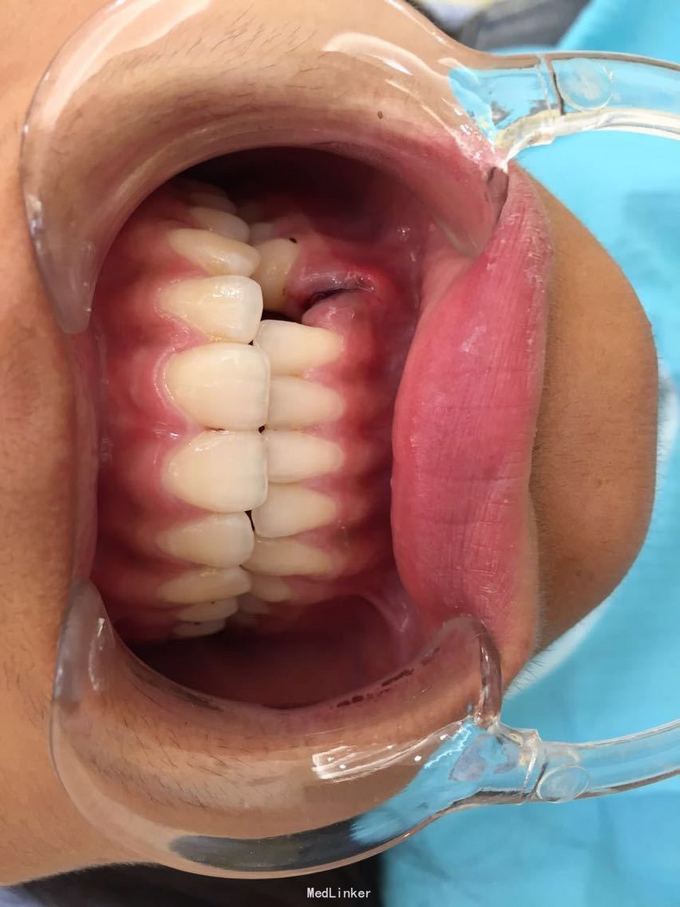

D3完全脱位,伤口血凝块已经凝固,颊侧牙龈钝性撕裂。D2D4无叩痛和松动。脱落牙齿牙体硬组织完好,牙周膜干裂,牙体上有纸屑和食物残渣,根尖有牙髓组织呈黑红色。

D3牙脱位 D3体外根管治疗后垫底充填,盐水和双氧水浸泡后,刮尽牙根的牙周膜后放置盐水和庆大霉素液中15分钟。局麻下刮除牙槽窝内血凝块至流鲜血后盐水和庆大霉素交替冲洗,明胶海绵拭干牙槽窝,浸泡好的牙体植入牙槽窝内并复位,舌侧树脂牙周夹板固定D123456,牙周上派丽奥。随诊